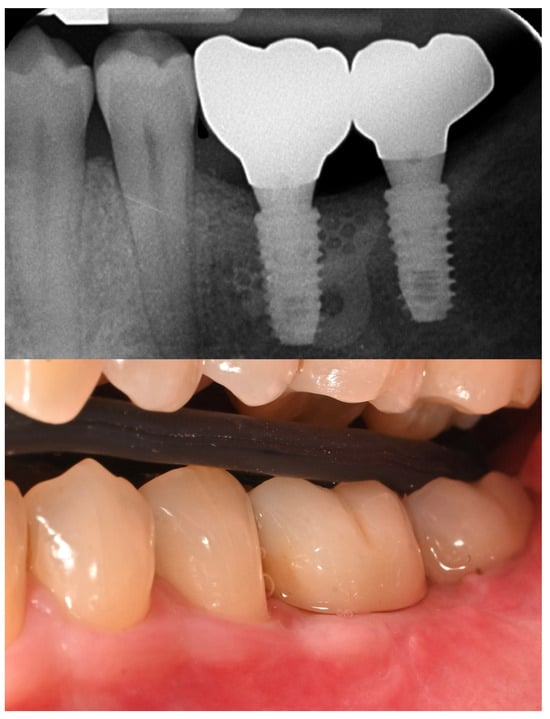

Nine months later, a periodical radiograph (Figure 6) and clinical examination confirmed adequate bone regeneration. Two implants (Osstem TSIII SOI, 4.5 mm in diameter and 10 mm in length; Osstem Implant Co., Ltd., Seoul, Republic of Korea) with hydrophilic surfaces were placed under local anesthesia, using a fully guided (Figure 7), metal-sleeve-free surgical template (OneGuide, Osstem Implant Co., Ltd., Seoul, Republic of Korea).

Figure 6. Postoperative intraoral radiograph.

Figure 10. Before and after prosthesis delivery. Two single monolithic zirconia crowns were delivered and bonded to titanium link abutments, ensuring functional and aesthetic rehabilitation.

The patient entered a 6-month hygiene maintenance protocol and continues to be monitored. One year after definitive prosthesis delivery, the implants were clinically stable, with no bleeding on probing. Radiographically, the bone remains stable, with no bone loss (Figure 11).

Figure 11. One-year radiographic and clinical follow-up.